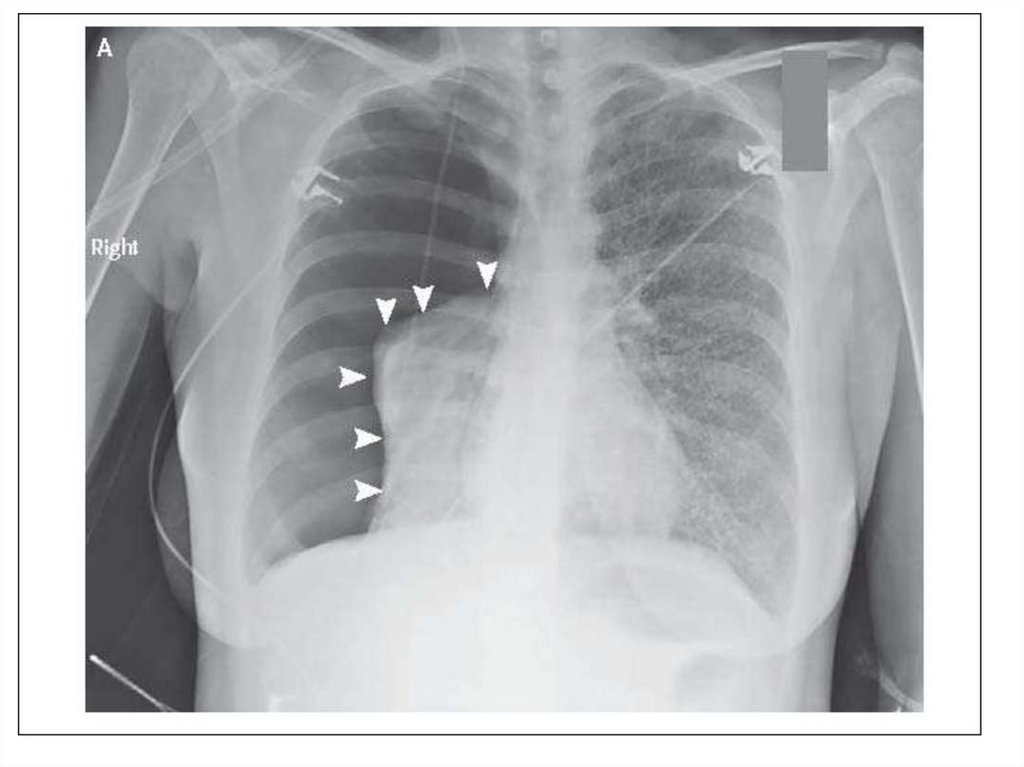

15. Наличие воздуха в плевральной полости

В большинстве случаев пневмоторакс - это

односторонний процесс. Может возникнуть в

результате травмы извне, либо спонтанно при

деструктивных процессах в легких. Имеет 3

механизма – открытый, закрытый, клапанный

(напряженный).

Видимая картина – поджатое к корню легкое,

смещение средостения в другую сторону.

Одностороннее просветление на стороне

поражения.

Напряженный пневмоторакс